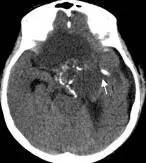

病例二:患儿女性,7岁,主因头痛2年,精神差1个月收入院。入院时头CT见典型的“超大型”颅咽管瘤,直径约9厘米,见图6。

图6.CT显示囊性颅咽管瘤

白色三角显示肿瘤边界